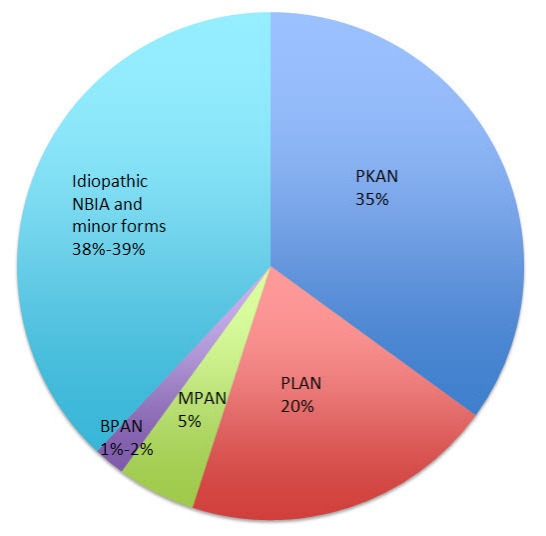

До 2001 года синдромом Галлевордена — Шпатца называли все формы NBIA, однако после открытия первого NBIA-ассоциированного гена от этого пришлось отказаться. Изученный ген исследователи связали с пантотенат-киназно связанной нейродегенерацией (Pantothenate kinase-associated neurodegeneration, PKAN) — самой распространенной формой нейродегенерации с отложением железа. В течение последующих лет были открыты и другие генные мутации и фенотипы нейродегенерации: в 2006 году была обнаружена мутация гена PLA2G6, кодирующего фосфолипазу А2, приводящая к возникновению PLA2G6-ассоциированной нейродегенерации (PLAN), в 2011 — ген C19orf12 был идентифицирован как ответственный за нейродегенерацию, ассоциированную с белками митохондриальной мембраны (MPAN). Еще более недавно в спектр NBIA включили еще одно заболевание: бета-пропеллерный белок-ассоциированную нейродегенерацию (BPAN). Вместе эти четыре подтипа нейродегенерации с отложением железа являются наиболее часто встречающимися и диагностируемыми (более чем 62 % от всех случаев).

Рисунок 2. Частота встречаемости подтипов NBIA.

В спектр также были включены еще 6 более редких подтипов: нейроферритинопатия, ацерулоплазминемия, болезнь Куфора — Ракеба, нейродегенерация, связанная с гидроксилазой жирных кислот (FAHN), синдром Вудхауза — Сакати и COASY-протеин-ассоциированная нейродегенерация (CoPAN). Большая часть заболеваний, объединенных термином NBIA наследуется аутосомно-рецессивно, за исключением BPAN и нейроферритинопатии, которые наследуются Х-сцепленно доминантно и аутосомно-доминантно соответственно.